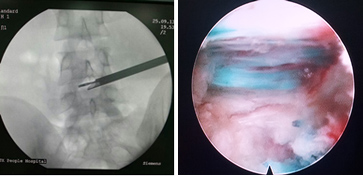

近日,江西省人民医院骨一科陈钢主任、龚飞鹏、龙智生两位主治医师共同为一例患者成功实施了椎间孔镜下椎间盘髓核摘除手术。该手术效果明显,创伤小,使我省脊柱外科微创水平上升了一个新的台阶。

患者是一名19岁青年,因右下肢放射痛入院,疼痛的范围为大腿及小腿后外侧,入院前曾接受多方治疗,牵引、药物及其他理疗均未见效,疾病严重影响其生活及工作,基本只能卧床休息。MRI检查示L4/5椎间盘右侧巨大突出,压迫神经。对这类患者,手术指征明确,传统手术方式为腰椎后路L4/5开窗髓核摘除术,手术创伤大,术中需要剥离后方肌肉,手术时间长,出血量大,术后恢复慢而且有可能遗留腰痛症状。对于这样年轻的患者,可能会对其今后的生活造成一定的影响。经过充分的术前准备,陈钢主任为该患者在局麻下实施了椎间孔镜下椎间盘髓核摘除,通过在椎旁13CM处C臂机监视下穿刺,定位椎间盘及椎间孔位置,放入内窥镜,在直视下将椎间盘完全摘除。由于使用局麻,患者可以在术中和主刀交流,自诉症状缓解情况,该患者术中即感觉症状明显缓解,手术结束时,患者十分高兴,因为原来不敢活动的右腿活动自如了。该患者住院两天后即步行出院。与传统手术比较,因为没有剥离肌肉及切除椎板,手术切口只有1CM,大大减轻了患者的病痛及减少了常规住院的时间。

椎间孔镜技术是真正的微创技术,并被国际脊柱外科界所承认是一种损伤最小、适应症最广的椎间盘突出/脱垂的治疗技术, 是新的脊柱外科发展趋势和重要发展方向。其采用In Side--Out Side技术,通过安全三角区进入椎间盘,摘除病变髓核后退至椎间孔外,清除脱出的碎片;中央型突出,压迫椎管超过上关节突连线的病例,采用远外侧水平入路,直接摘除突出组织;游离型、黄韧带肥厚、钙化、椎管狭窄、神经孔狭窄等病例,采用椎间孔内入路,可摘除各种病变软组织、清理骨质;可以处理所有类型的椎间盘突出,还可以处理骨质,可做椎间盘复发的微创翻修手术(对于开放手术后复发的,MED手术后复发的),配合经皮固定技术可以完成退变疾病的治疗;椎间孔镜(是整体外径仅有6.3mm的同轴内窥镜,并配备有灯光、器械工作通道、注水及冲洗通道)仅需7mm的皮肤切口,从病人身体侧方、侧后方、后方,采用水平、倾斜、垂直的入路方式,通过椎间孔直达椎间盘突出部位,在椎间盘纤维环之外做手术,不伤及椎板及黄韧带,不影响脊柱稳定性,在内窥镜直视下可以清楚的看到突出的髓核、神经根、硬膜囊和增生的骨组织,然后使用各类专用的抓钳摘除突出组织、镜下去除骨质并配合射频电极进行盘内消融、术中止血及封堵破损纤维环。创伤小:皮肤切口仅7mm(如同一个黄豆粒大小),术中出血不到 5ml,术后仅缝1针(亦可不进行缝合处理),是同类手术中对病人创伤最小、效果最好的治疗腰椎间盘突出的终极微创手术。